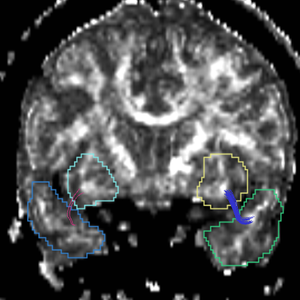

Region

caseD00917

caseD00920

caseD00924

caseD00928

caseD00935

caseD00936

caseD00938

caseD00939

caseD00940

Uncinate Fasciculus

Internal Capsule

Fornix

Cingulum

Arcuate Fasciculus